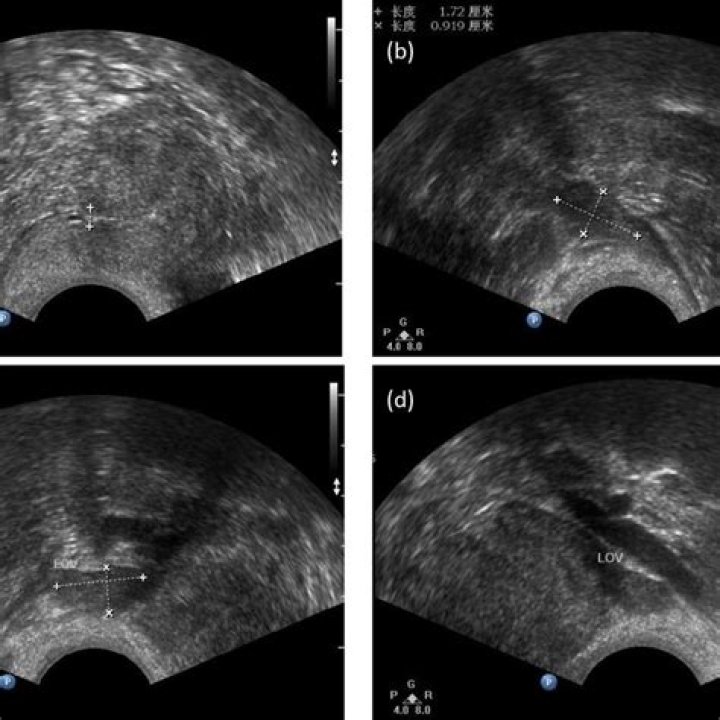

More reliable markers for POI diagnosis are AMH levels and AFC on days 4–8. A transvaginal ultrasound imaging of the ovaries is one of the relevant diagnostic tests in patients with POI.

There are two good ways to measure egg count: an antral follicle count and an AMH (anti-Müllerian hormone) test. During an antral follicle count, a doctor uses ultrasound to count the visible follicles. Each follicle contains an immature egg that could potentially mature and ovulate.